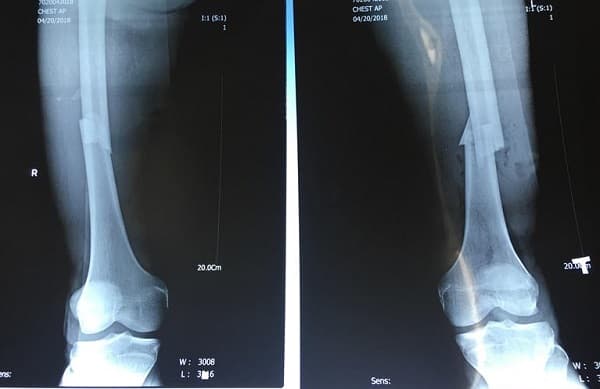

Gãy xương mác có cần bó bột không và cần phải chú ý gì?

Trong các chấn thương xương khớp ở chân, gãy xương mác là trường hợp thường gặp. Vậy gãy xương mác có cần bó bột không? Gãy xương mác có cần bó bột không? Theo các bác sĩ cơ xương khớp, xương mác là xương phụ, chỉ chiếm 17% trọng lượng cơ thể. Xương mác có […]